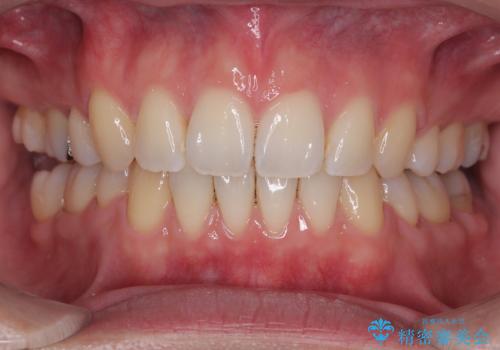

- 下の前歯のデコボコと、口元の突出感を改善したいと来院された患者様です。

突出感の強い上顎前歯をしっかりと後方移動させるため、上顎の裏側の補助装置(リンガルアーチ)とアンカースクリューを併用しています。

上下左右の第一小臼歯を抜歯して、目立ちにくいワイヤー装置で矯正を行いました。

上下の保定用マウスピースの他に、デコボコの強かった下顎前歯にはワイヤーで保定をしています。